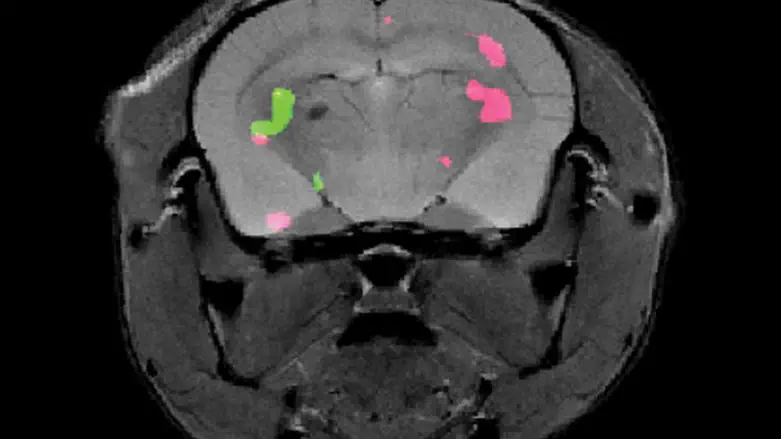

Dr. Hyla Allouche-Arnon, a staff scientist in Bar-Shir’s lab, led the study, in which Bar-Shir’s team and other researchers collaborated with Prof. Sarel Fleishman and Dr. Olga Khersonsky of Biomolecular Sciences Department. Applying the method in live mice, the scientists used exceptionally powerful MRI equipment with a magnet of about 15 tesla – one of only a handful of such machines in the world. The scans picked up the frequencies of the molecular probes, revealing the exact positions of the cells that expressed each of the proteins and marking them in green and pink.